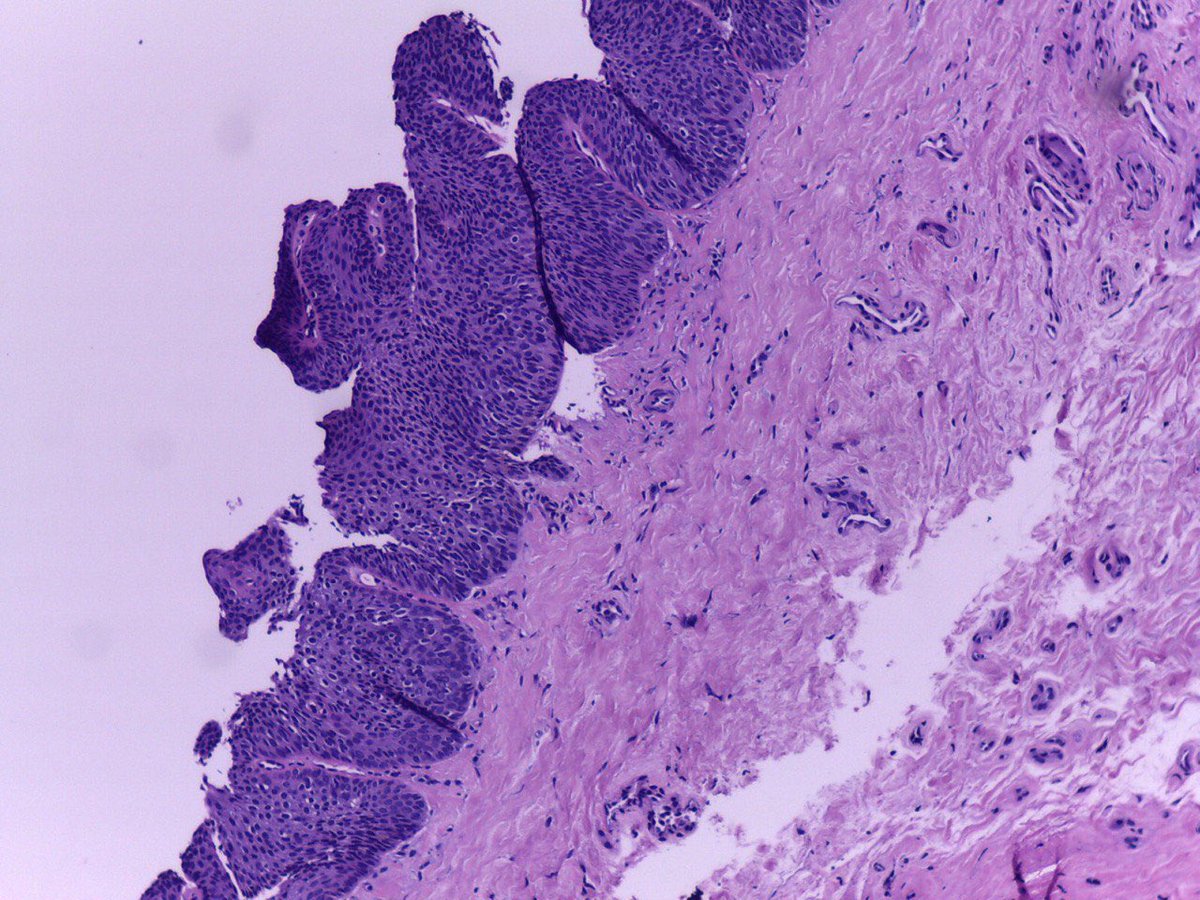

Esta es una #verruga viral de la planta del #pie #ojodepescado #dermatología #dermatopatología, a veces se toma biopsia. Acude a revisión de #dermatología #dermatopatología

7

16

61